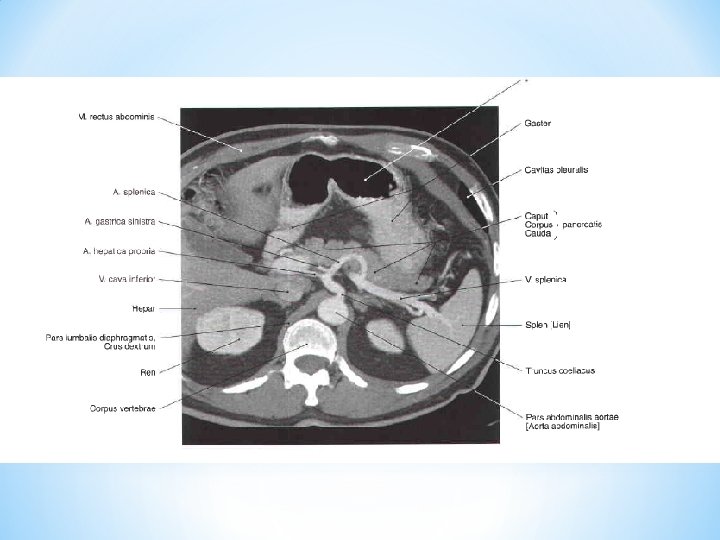

PANCREAS Caput, corpus, cauda, incisura pancreatis, processus uncinatus (a. et v. mesenterica sup. )

Exocrine pancreas: Endocrine pancreas: ductus pancreaticus insulae pancreaticae ductus pancreaticus accessorius (islets of Langerhans) succus pancreaticus insulin, glucagon

ERCP – endoscopic retrograde cholangio-pancreatography